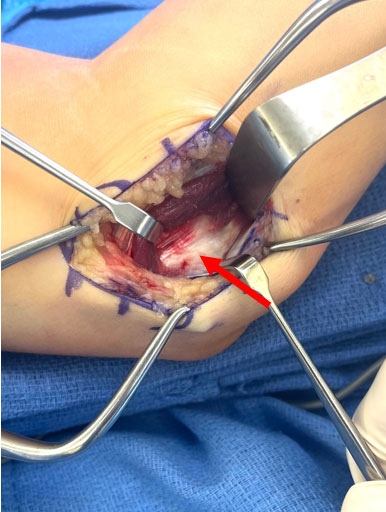

Medial approach to elbow is utilized

A muscle splitting approach is utilized to expose the ulnar collateral ligament (red arrow)

The ligament is incised, and a proximal avulsion of the ligament is identified